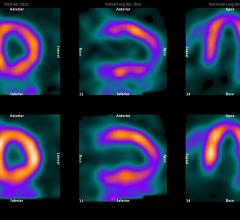

The last decade has seen a significant advancement in imaging technology due to developments in the hardware and software space. It was clear to the radiologists, clinicians and imaging scientists very early on that no single imaging modality, be it magnetic resonance imaging (MRI), computed tomography (CT) or positron emission tomography (PET) could meet all the needs of a clinician treating a patient.

The introduction of hybrid technology — positron emission tomography/computed tomography (PET/CT) and single-photon emission computed tomography (SPECT)/CT -— has revolutionized the imaging world. This technology allows the combination of the exquisite anatomic details provided, for example, by CT, with the important and much needed functional, physiologic or metabolic information provided by molecular imaging.

The BrightView XCT is a single photon emission computed tomography/computed tomography (SPECT/CT) imaging system designed to provide quality, efficiency and accuracy. Full iterative technology (FIT) in SPECT and CT uses advanced algorithms for the truest picture possible.